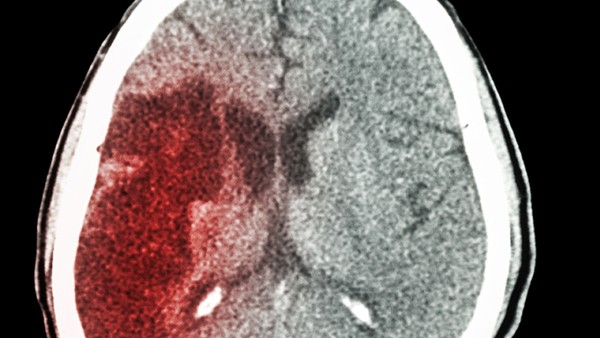

脑出血是神经内科常见的脑血管疾病,由于脑动脉破裂引起的颅内出血。治疗不及时,患者可能会昏迷、瘫痪,不能不重视,脑出血后患者的护理也很重要,好的护理,患者的并发症减少,特别是褥疮、肺部感染等。患者保持良好的心情,积极配合医生的治疗,有助于疾病的恢复。